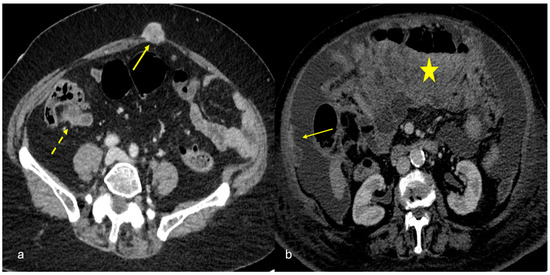

3.1.5. Peritoneal Lymphomatosis

3.1.6. Mesenteric Metastases from Ileal Neuroendocrine (Carcinoid) Tumors